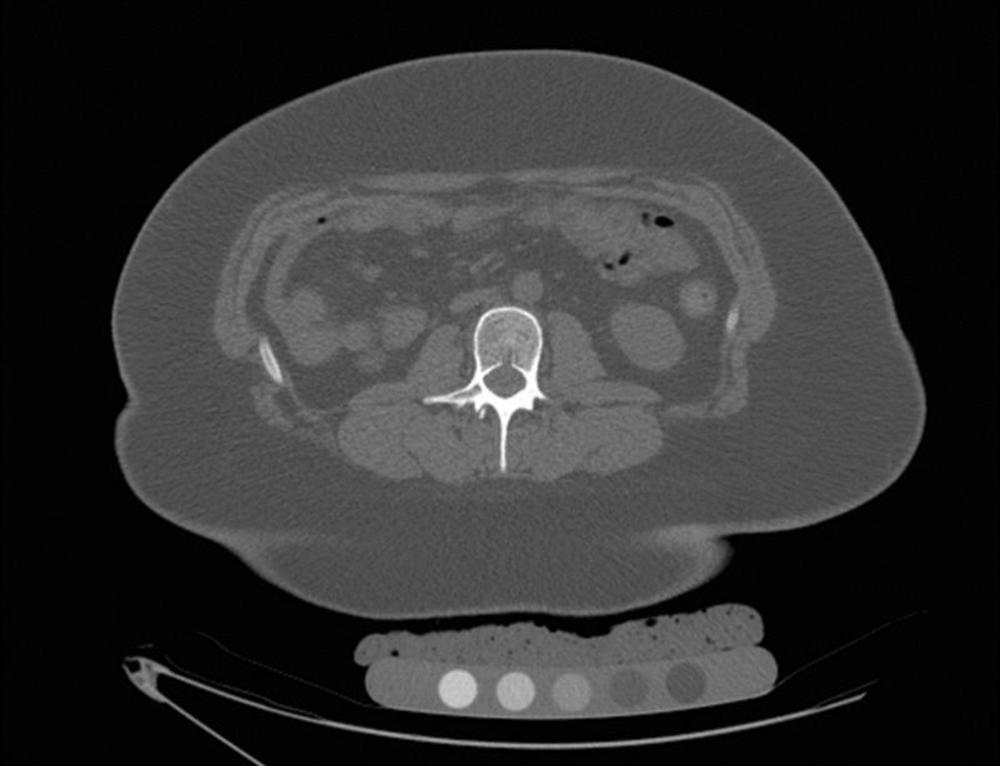

Figure 1. CT in a 17-year-old female prior to sleeve gastrectomy. Volumetric bone mineral density pre-surgery was 183 mg/cm3.

High-res (TIF) version